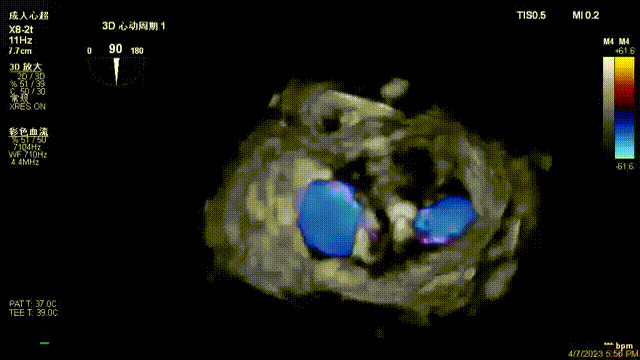

接受治療的是一例器質(zhì)性重度二尖瓣反流(DMR)患者,主訴“反復(fù)活動(dòng)后胸悶,氣促3年余”。術(shù)前超聲顯示,雙房增大,二尖瓣脫垂伴重度反流,輕度三尖瓣反流,輕度肺高壓,升主動(dòng)脈增寬。手術(shù)經(jīng)股靜脈-房間隔入路,采用全身麻醉插管,在TEE和DSA引導(dǎo)下完成房間隔穿刺。置入JensClip瓣膜夾系統(tǒng)后,在左房調(diào)整瓣膜夾的位置和軸向,后進(jìn)入左室,在TEE引導(dǎo)下捕捉二尖瓣前后瓣葉,并關(guān)閉瓣膜夾。經(jīng)TEE反復(fù)確認(rèn)手術(shù)效果后最終鎖定并釋放瓣膜夾。術(shù)后即刻超聲顯示瓣膜夾位置穩(wěn)定,功能良好,術(shù)前二尖瓣反流4+,術(shù)后0反流,肺靜脈逆流和左房壓都顯著好轉(zhuǎn),手術(shù)圓滿(mǎn)成功(以上數(shù)據(jù)都來(lái)源于醫(yī)院的臨床記錄)。術(shù)后患者狀態(tài)良好,目前已安排出院。

術(shù)后超聲顯示二尖瓣反流消失,瓣膜夾穩(wěn)定